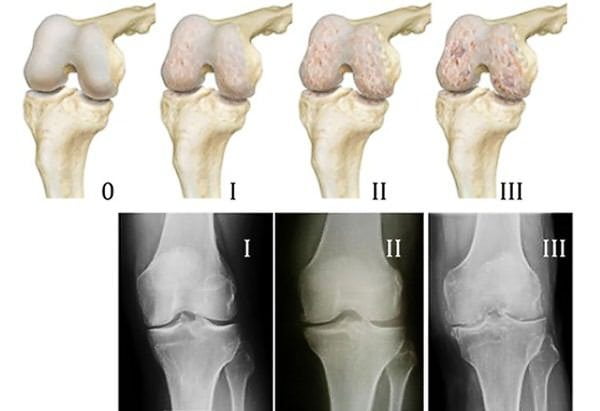

В Институте ревматологии РАМН были проведены 3-летние клинические испытания, в которых участвовали 20 добровольцев. У каждого из них был диагностирован гонартроз на различных стадиях течения. Основной целью исследования было установление клинической эффективности препарата Терафлекс Адванс. Терапевтическое действие врачи оценивали по следующим критериям:

Сотрудники Института ревматологии РАМН рекомендовали включать препарат в терапевтические схемы пациентов с суставными патологиями. Наиболее актуально его применение на начальных стадиях артроза, остеопороза, остеохондроза. В результате клинического исследования было установлено, что использование Терафлекс Адванс в лечении молодых пациентов приводило к более быстрому выздоровлению.

Основными показаниями к использованию Терафлекс Адванс становятся остеохондрозы шейного, грудного, поясничного отделов позвоночника и остеоартрозы. Но в ревматологии и ортопедии практикуется значительно более широкий спектр его применения. Препарат назначается пациентам, у которых диагностированы следующие патологии опорно-двигательного аппарата:

- гонартрозы;

Терафлекс Адванс используют для лечения заболеваний крупных суставов — тазобедренного, голеностопного, коленного, плечевого. Он эффективно предотвращает разрушение структурных составляющих сочленения независимо от стадии течения патологии. В травматологии препарат применяется для восстановления тканей после тяжелых вывихов или переломов.